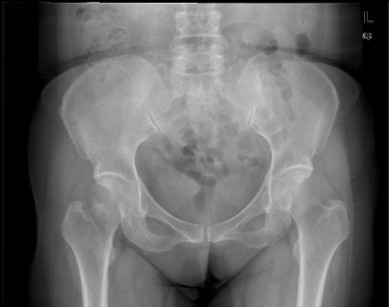

患者女,61岁,因“摔伤致右髋关节疼痛、活动受限9小时”入院。患者于入院前9小时行走时不慎摔倒,右侧肢体着地,当即感右髋关节及右大腿上段疼痛,活动受限,不能自行站立,受伤时及伤后无昏迷,无恶心、呕吐,无心累、气促,无腰痛及肉眼血尿。因休息后无缓解,急诊到当地医院行骨盆平片提示“右股骨颈骨折”,未做任何治疗,患者为求进一步治疗,遂急诊来我院,急诊以“右股骨颈骨折”收入住院。

查体:右髋关节、右大腿皮肤完整性好,右下肢轻度外旋。右腹股沟中点压痛明显,右股骨无明显压痛,未扪及明显骨擦感。右髋关节主被动活动受限。右下肢较左下肢短缩1cm。 辅查:院外X片右股骨颈骨折。

诊断:1、右股骨颈骨折(Garden III);2、骨质疏松症 治疗:择期手术